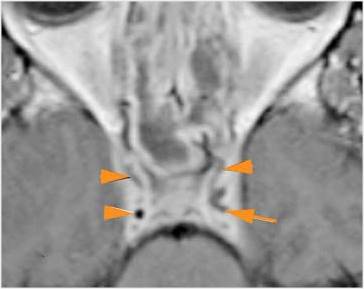

Intracranial

There is a subperiosteal fluid collection or abscess along the boney walls of the anterior or middle cranial fossa.

There is an epidural fluid collection or abscess along the boney walls of the anterior or middle cranial fossa.

There is a subdural fluid collection or abscess along the boney walls of the anterior or middle cranial fossa.

There is a subdural fluid collection or abscess along the falx cerebri or within the tentorium.

There is evidence of thrombus, thrombophlebitis or other occlusive or inflammatory process of the cavernous sinus.

There is evidence of inflammation of the distal internal carotid artery.